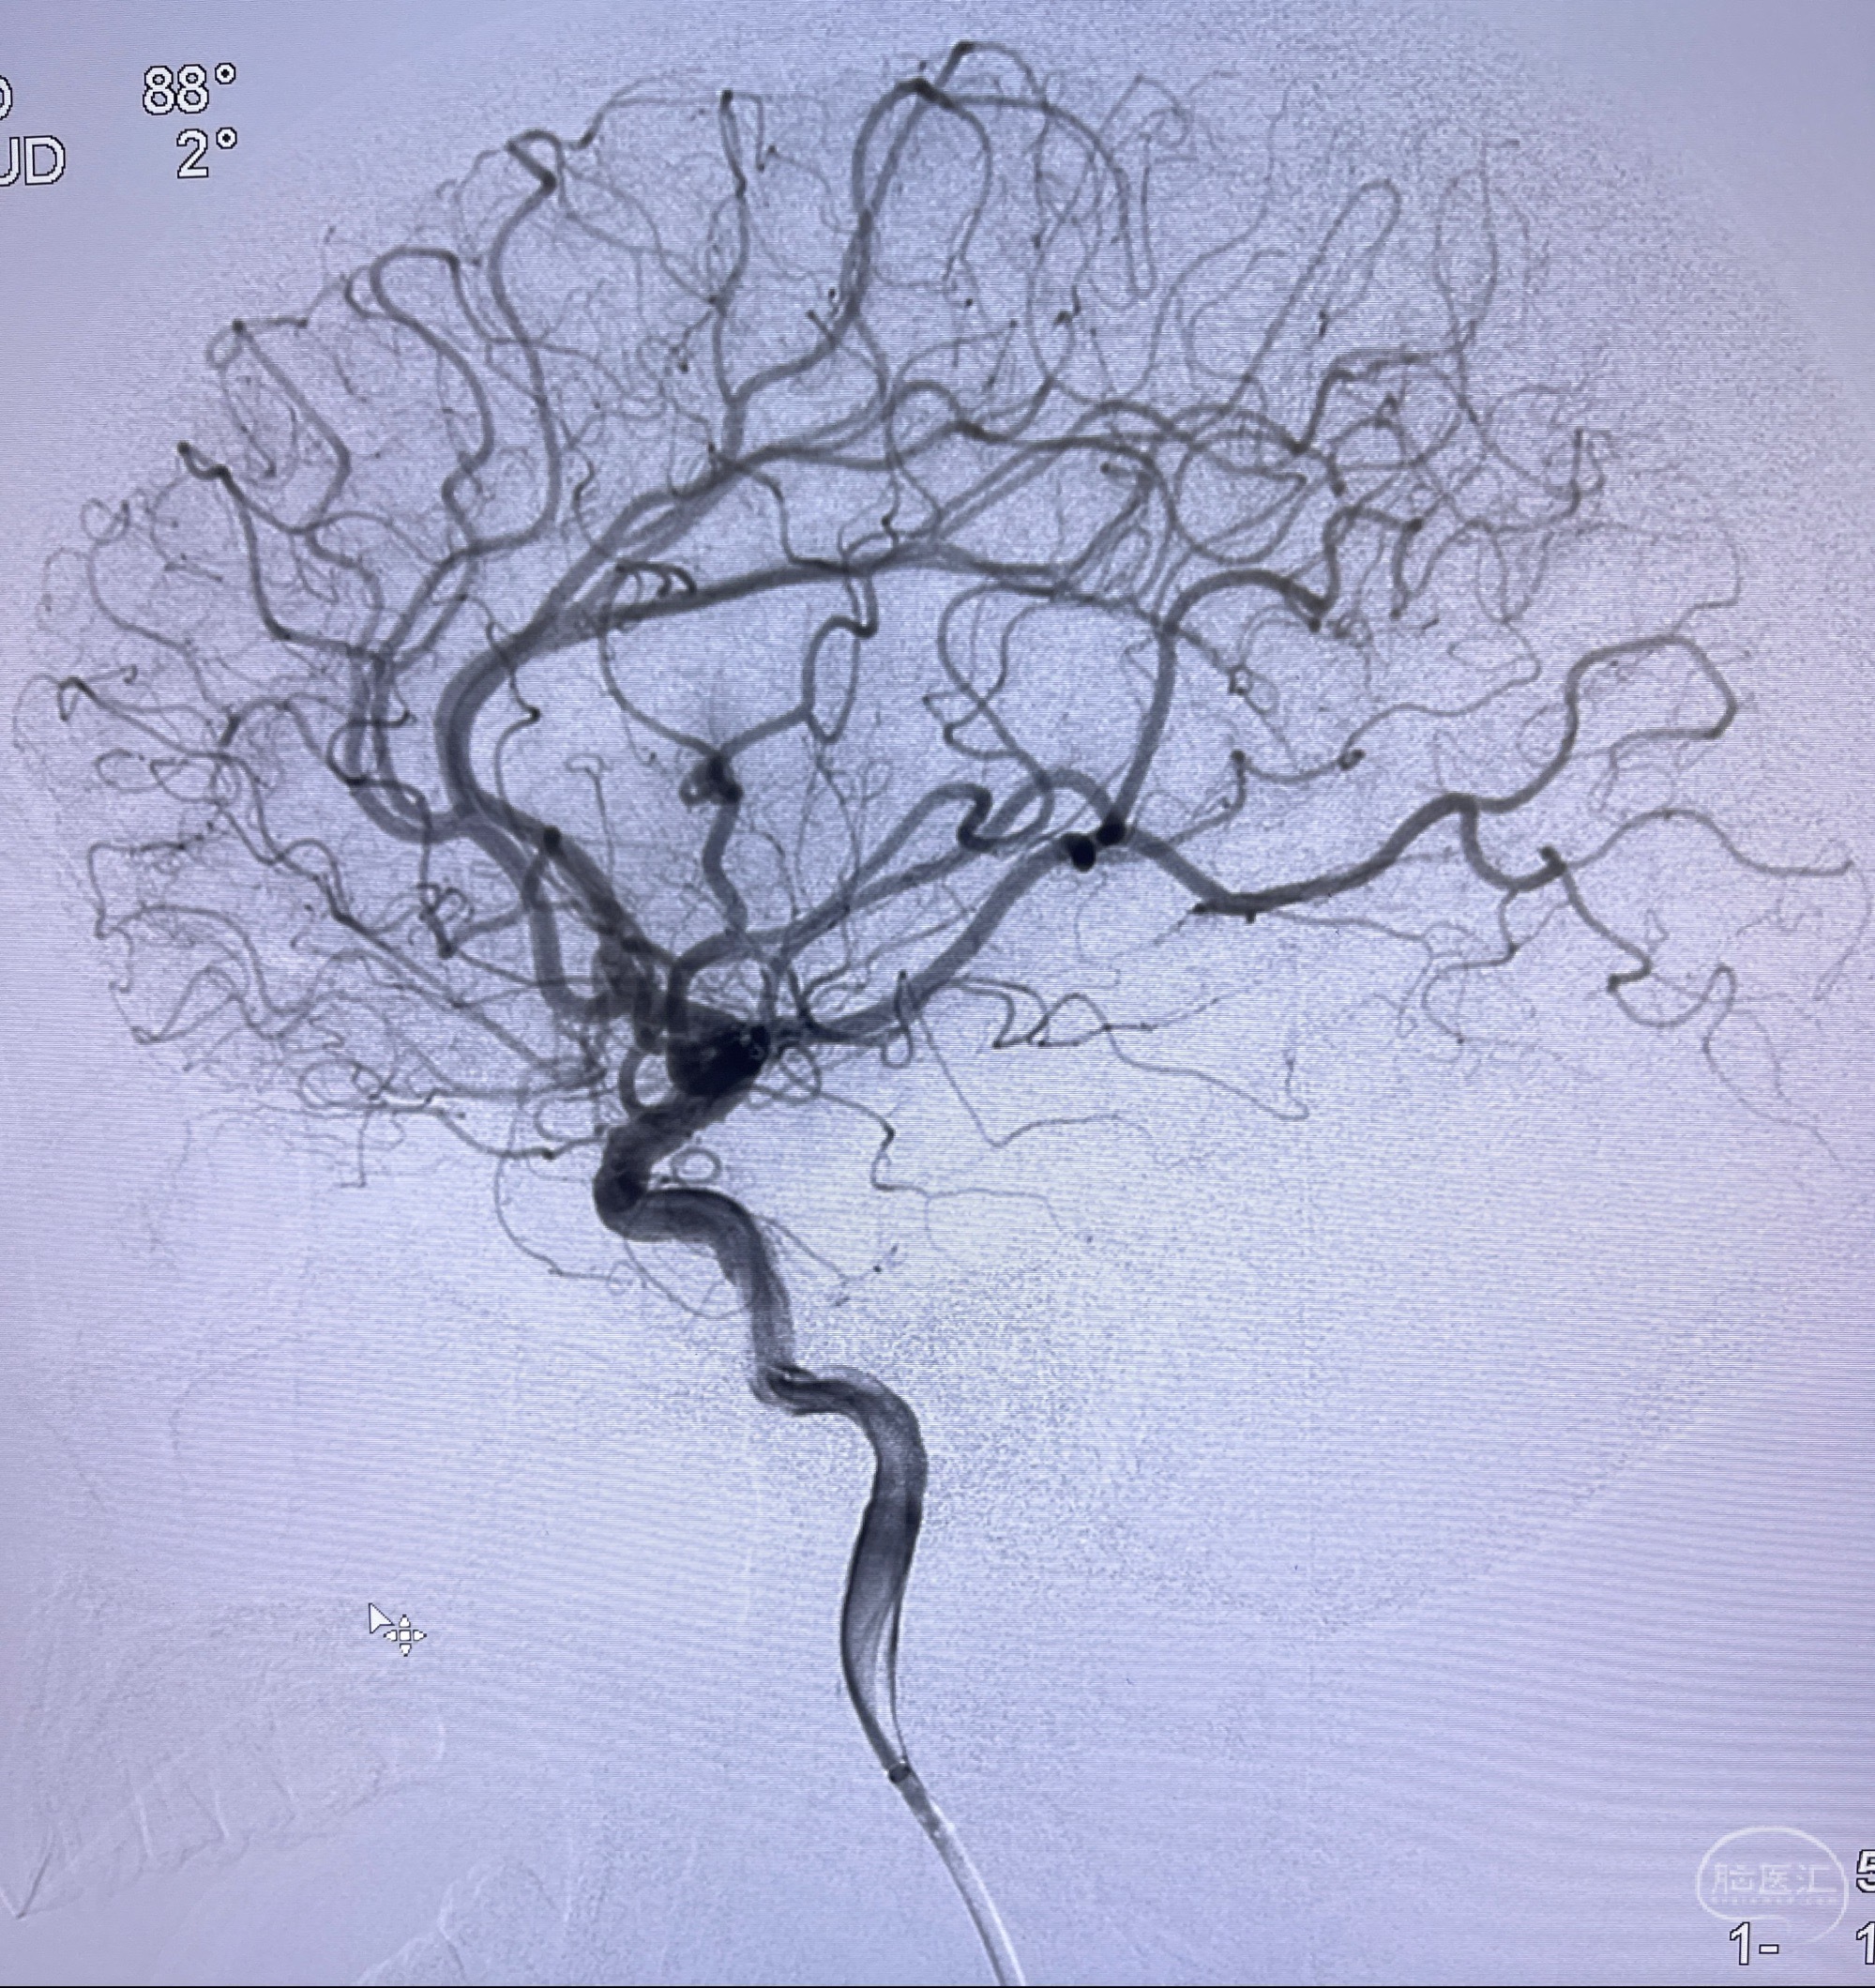

2023-08-14DSA:

左侧大脑中动脉动脉瘤,约2.6-2.8-3.4-2mm大小(瘤颈部、瘤体部、瘤高)

1.左侧大脑中动脉动脉瘤,约2.6-2.8-3.4-2mm大小(瘤颈部、瘤体部、瘤高)